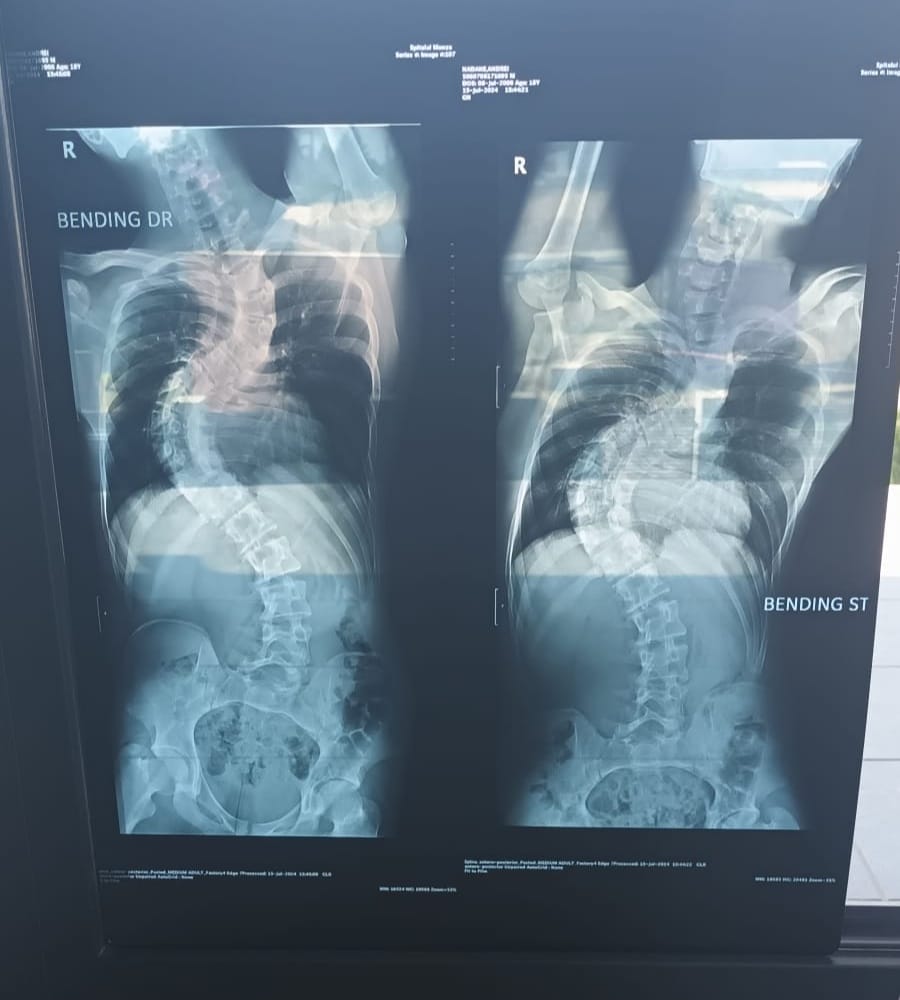

Un cavaler plin de speranțe și cu un viitor înainte suferă de Scolioză T7-T12.

Din păcate toate tratamentele și terapiile au fost fără succes

Însă la București șansele sunt mai mari și poate fi operat la Spitalul Monza.